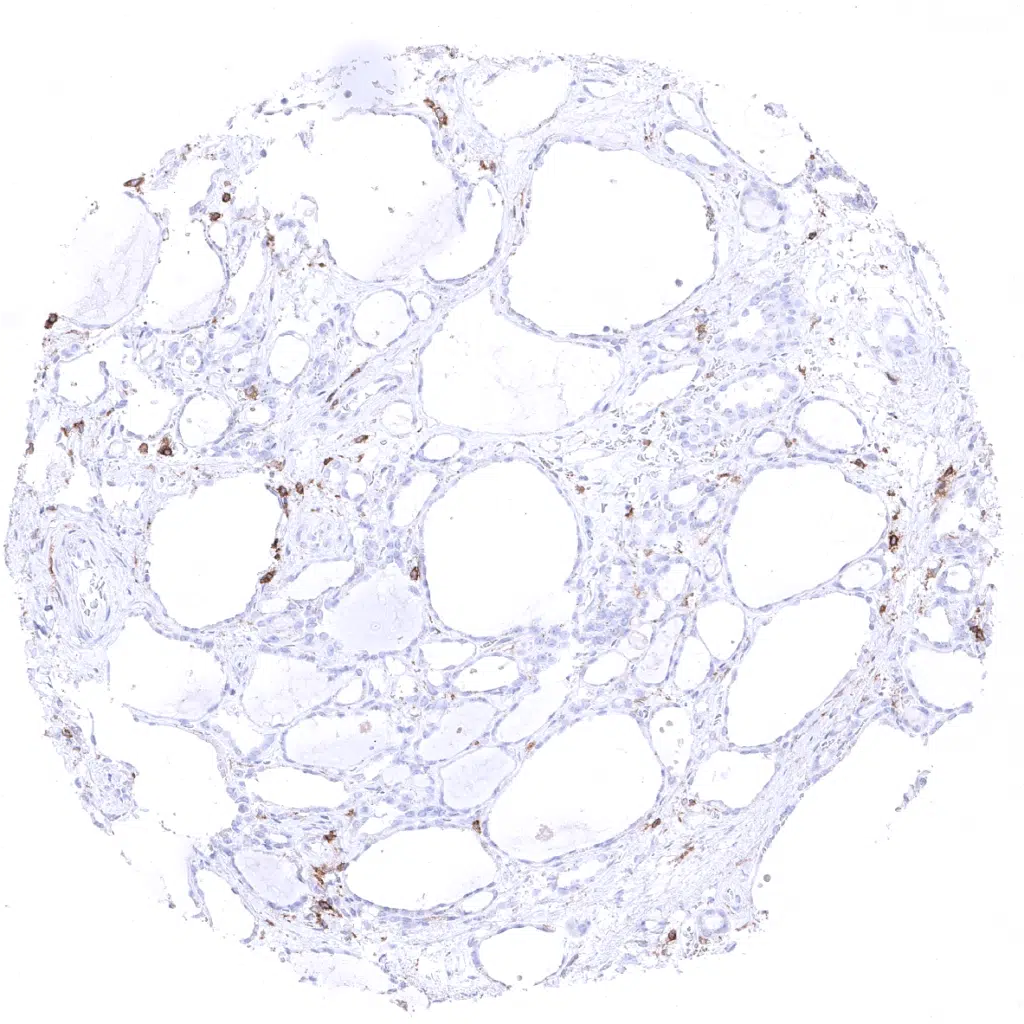

Lymph node - CD4 immunostaining is seen in a large subset of interfollicular T-lymphocytes of lymph nodes.